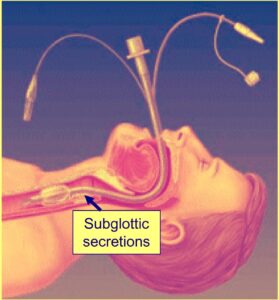

- Isolates airway, preventing aspiration

- Allows suction of the airway

Confirming correct placement of a tracheal tube

- Direct visualisation at laryngoscopy

- Ascultation (bilaterally, mid-axillary line, over the epigastrium)

- Symmetrical movement of the chest during ventilation

- Capnometry (recording the carbon dioxide concentration of exhaled air at the patient’s airway using a capnometer)